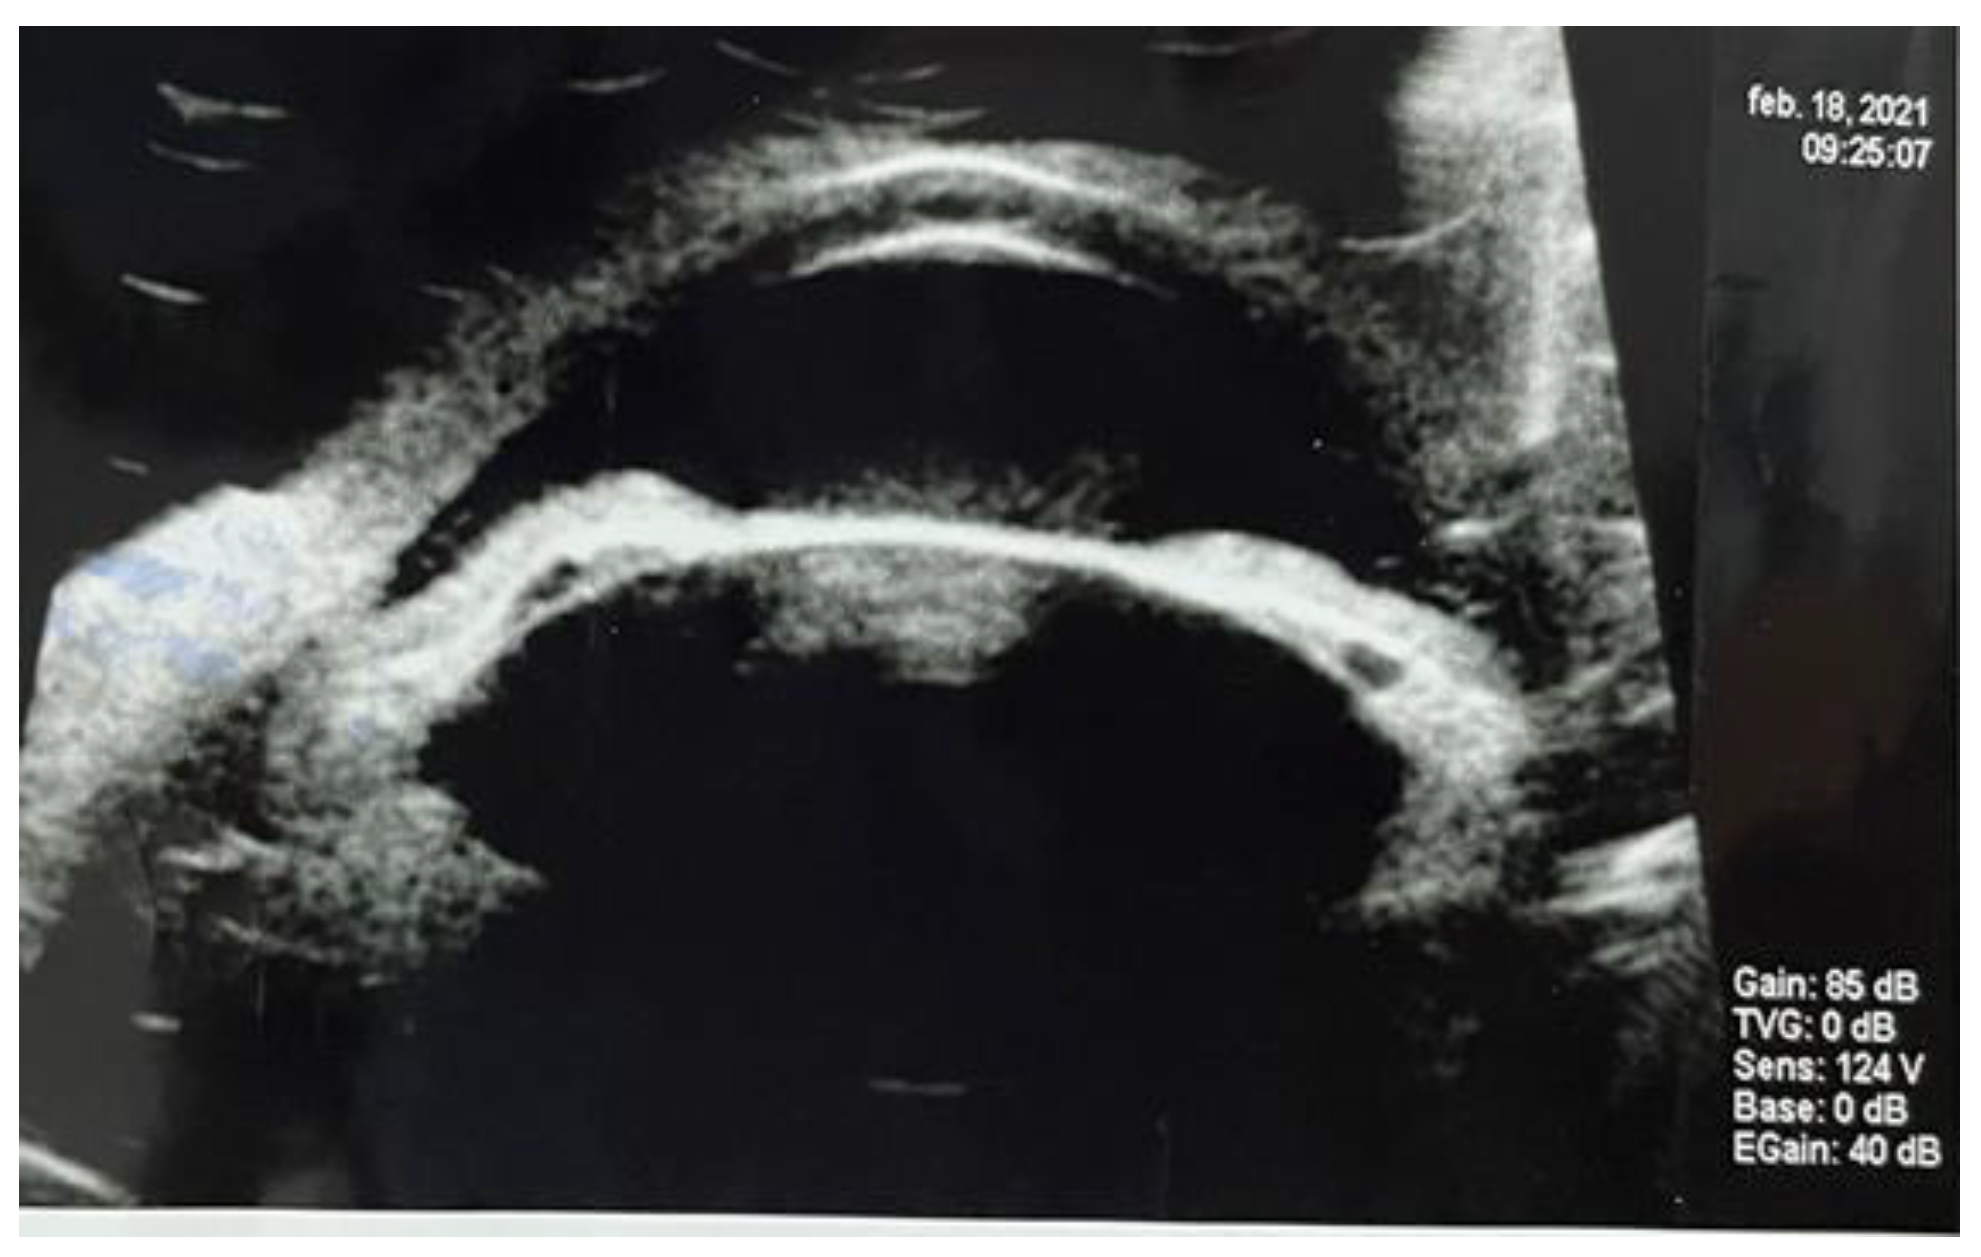

Thoraco-abdominal computer tomography was performed to identify the focus of the primary infection, in a patient with no other organ specific symptomatology. A multiloculated, non-homogenous hepatic abscess located in the right lobe, segment VIII, of 50/32/57 mm diameter, surrounded by a hypodense area. The paraclinical data confirmed the general inflammatory syndrome, with and ESR (12 mm/h), leukocytosis 15.7/30*3/microL with neutrophilia 84.2%, and showed mild increase of hepatic enzymes: AST (85UI/L), GGT (113 UI/l). Blood culture were obtained, but could not identify any pathogenic agent. IG ELISA for Echinococcosis was negative. Infectious disease and general surgery evaluation recommended empiric general antibiotherapy was initiated with intravenous Ceftriaxone 1 g/day, switched after 5 days to meropenem 1g at 8 hours and Vancomycin 1 g at 12 hours for, for 14 day. Progressive remission of the hepatic liver abscess was observed on serial computer tomography (Figure 4).

Figure 4.

Serial CT exam: diminished size of the right lobe hepatic abscess: a) after intravenous therapy; b) at admission.